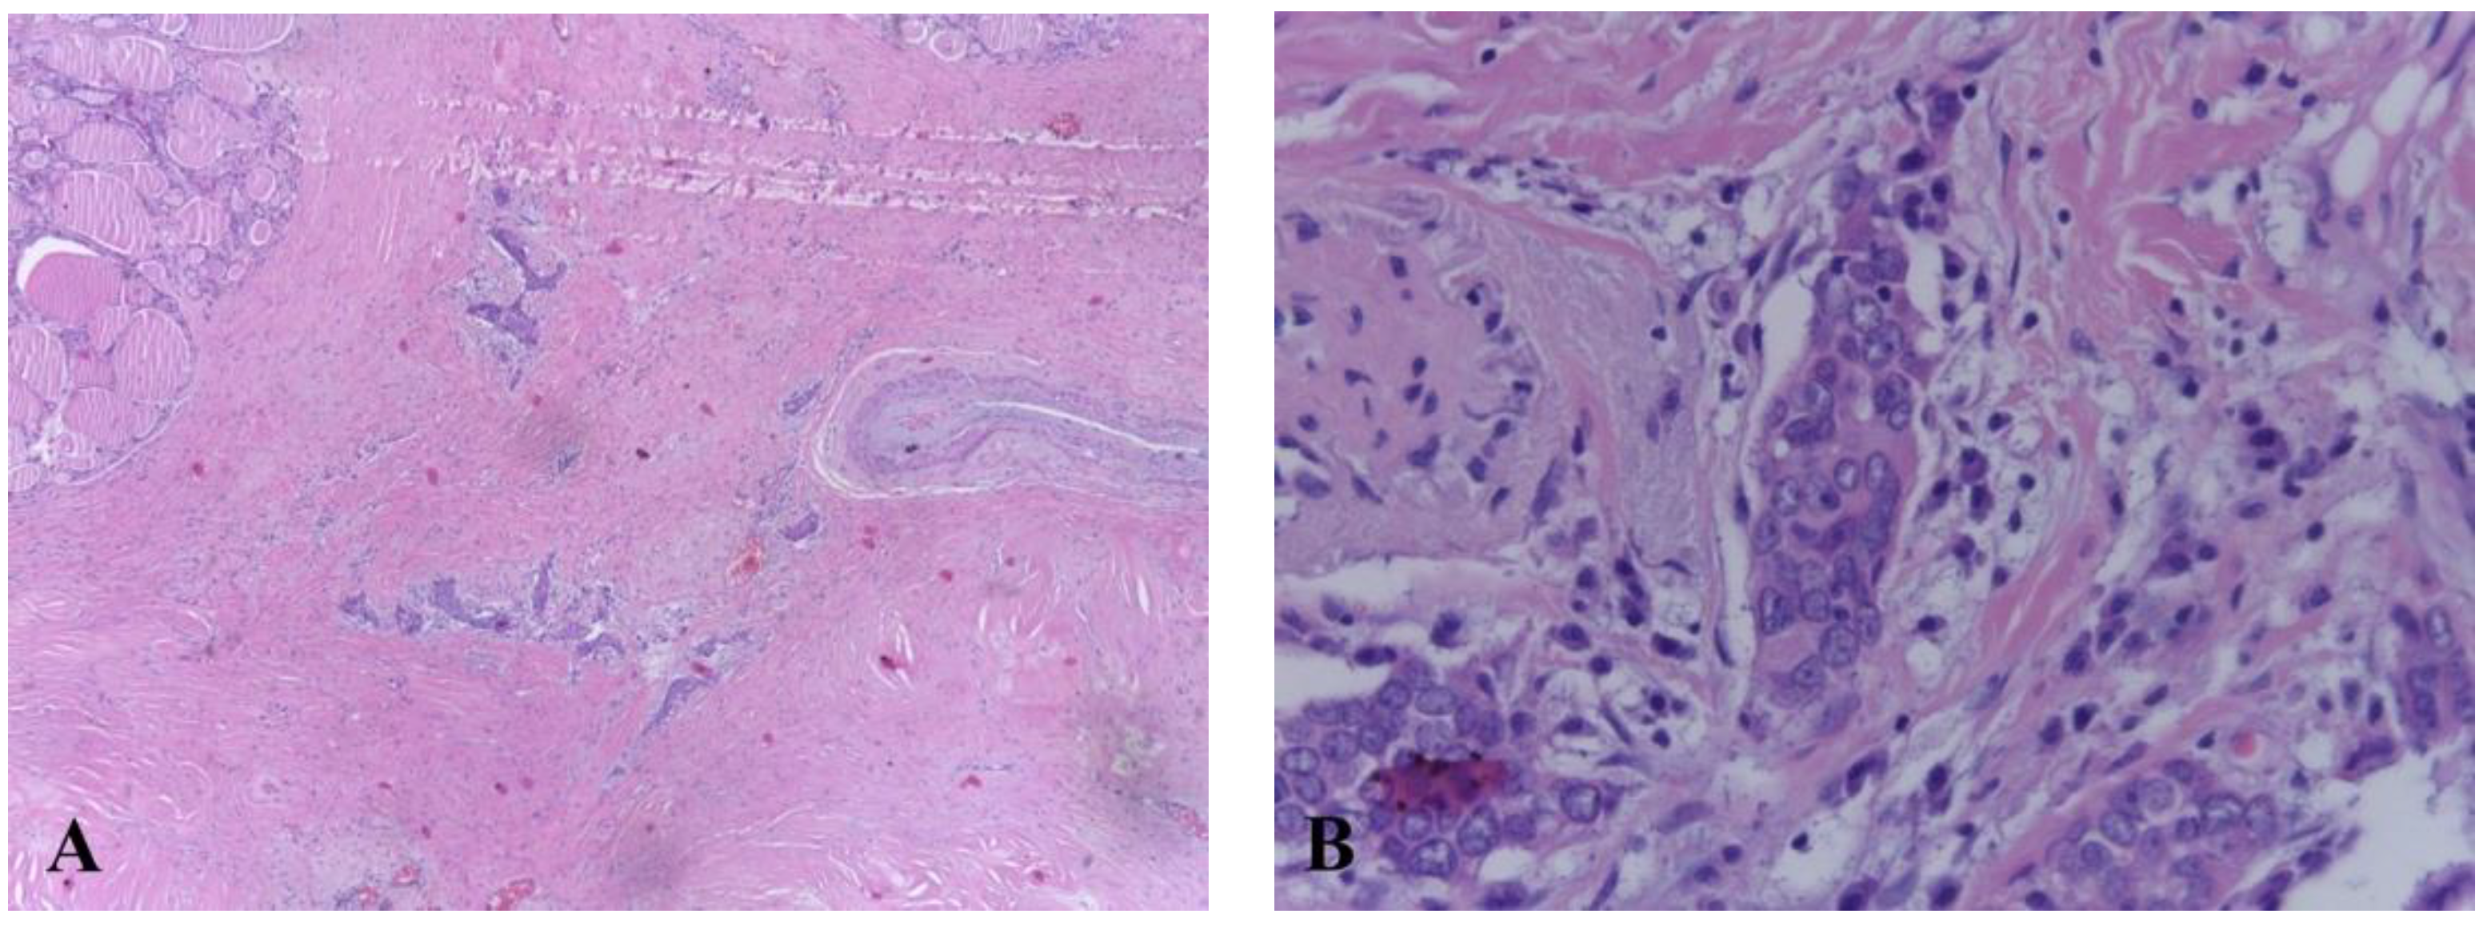

2. Case Report